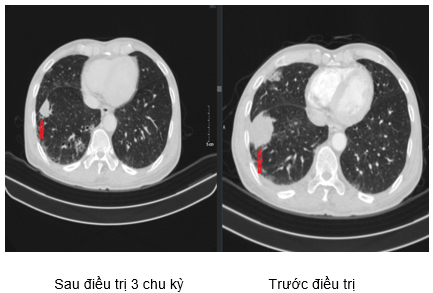

Hình 3. Hình ảnh tổn thương thùy trên phổi trái: Sau 3 chu kỳ điều trị (hình bên trái) giảm kích thước so với trước điều trị (hình bên phải).